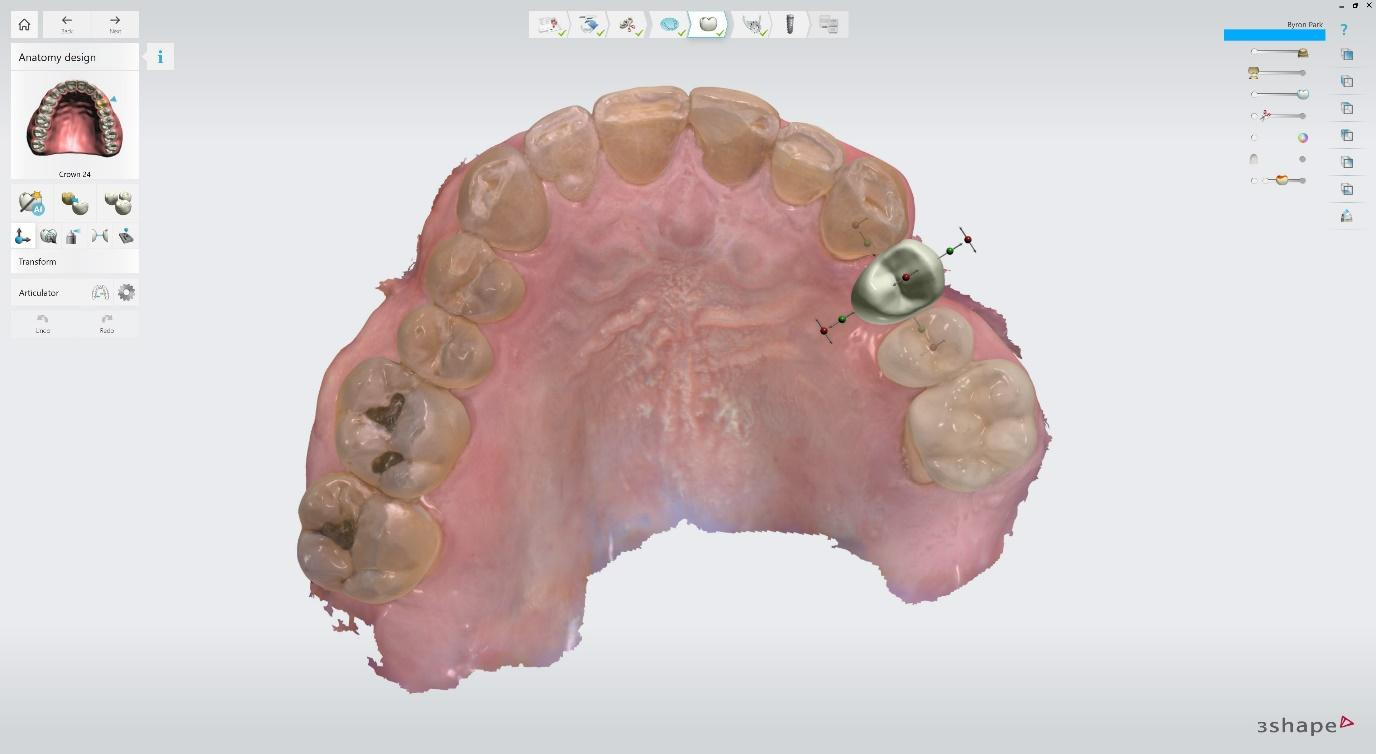

Digital impressions were captured using the TRIOS 4 intraoral scanner, and the implant-supported crown was designed using 3Shape Design Studio.

Implant detection matches the scan body in the intraoral scan with the digital library. A colour scale is given to show the accuracy of the matching (Green is good).